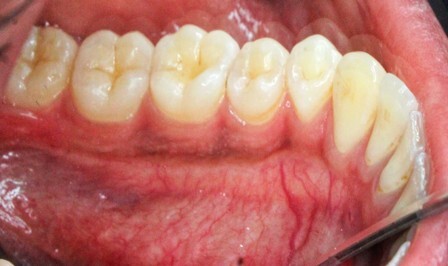

The MGJ was delineated by the visual method and the roll method following clinical examination in dental chairs appropriately equipped. Visual assessment relies on identifying the color difference between the gingiva and alveolar mucosa. The mucosa beyond the MGJ typically appears darker red compared to the AG, helping to demarcate the MGJ. The rolling probe method entails pushing the neighboring alveolar mucosa coronally with the blunt end of a probe. It is a functional assessment method that aids in determining the boundary between gingiva and movable mucosa.10 The probing sulcus depth was subtracted from the measured KG width at the mid-lingual aspect of each tooth to determine the width of AG, and all fractional measurements were rounded off to the nearest whole number of millimeters (Figure 1 through Figure 3).

Fig 1 through Fig 3. Measurements of lingual attached gingiva: Fig 1 = identifying the MGJ.

Fig 2 = sulcus depth measurement.

Fig 3 = determining width of keratinized gingiva.

Fig 4 through Fig 6. Lingual attached gingiva in a male subject: Fig 4 = left side.

Fig 5 = middle.

Fig 6 = right side.